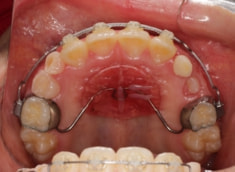

治療法:上顎拡大装置+フルパッシブブラケット(クリアスナップ)+フェイスマスク等

解説:上顎の急速拡大により、骨格的に拡大、前方牽引を促します。

治療前